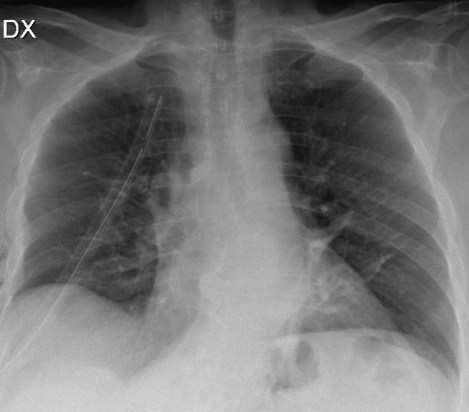

No complications were observed; post-operative chest x-ray shows good lung expansion and a normal cardiac silhouette (Fig. 8).

Figure 8. Post-operative chest x-ray shows good lung expansion and a normal cardiac silhouette